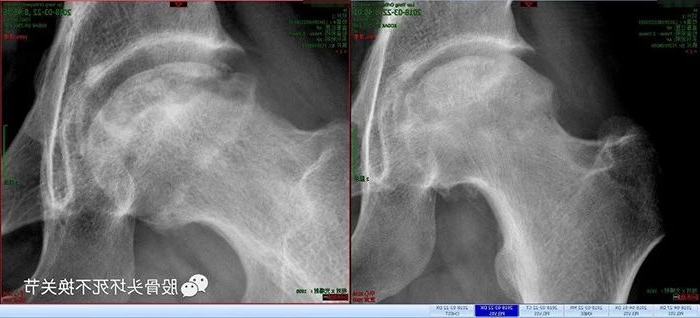

这是一位30岁的男性患者,病人自述有15年的饮酒史,右胯(髋)关节疼痛、活动受限1年、左髋关节疼痛1年。临床诊断:双侧股骨头坏死。

左侧股骨头内大面积囊性变,波及外侧柱。

CT影像证实右侧股骨头关节面几近碎裂,股骨头前侧可见大面积囊性变空洞,髋臼缘及股骨头边缘可见骨质增生;左侧股骨头囊性变范围也非常大,几乎就剩余一个空壳,塌陷危险性非常高。